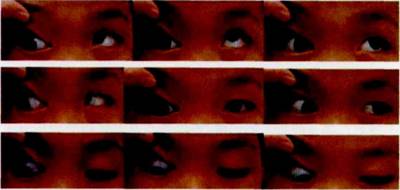

查体:裸眼视力(UCVA):右眼0.1,左眼1.0;屈光度:右眼+1.50—0.75×l2,左眼+1.00-0.50×172。角膜映光法:-15ºL/R15º。第一眼位为右眼下斜:左眼为主视眼。交替遮盖:右眼外下至正中,左眼外上至正中。左眼注视时,伴右眼睑下垂并右眼下转(见图 1A)。有眼注视时,右眼睑下垂消失并左眼上转。双眼球运动:右眼内上、上方、外上方均上转受限(-2)(见图2)。双眼Bell征(+),右侧减弱。患儿咀嚼时,右上睑呈节律性上抬(见图 1A-B),伴有右侧附耳(见图1C)。交替遮盖加三棱镜法:5 m 和33 cm 检查距离均为-30△L/R30△。右下睑约1/2 睫毛倒人眼球。

A,咬合时右眼睑下垂;B,张口时右眼睑上抬;C,右侧附耳

图l 患儿右眼下斜视并右侧 Marcus-Gunn综合征伴右侧附耳

图2 单眼双上转肌麻痹伴下颌-瞬目综合征患儿术前9个诊断跟位图